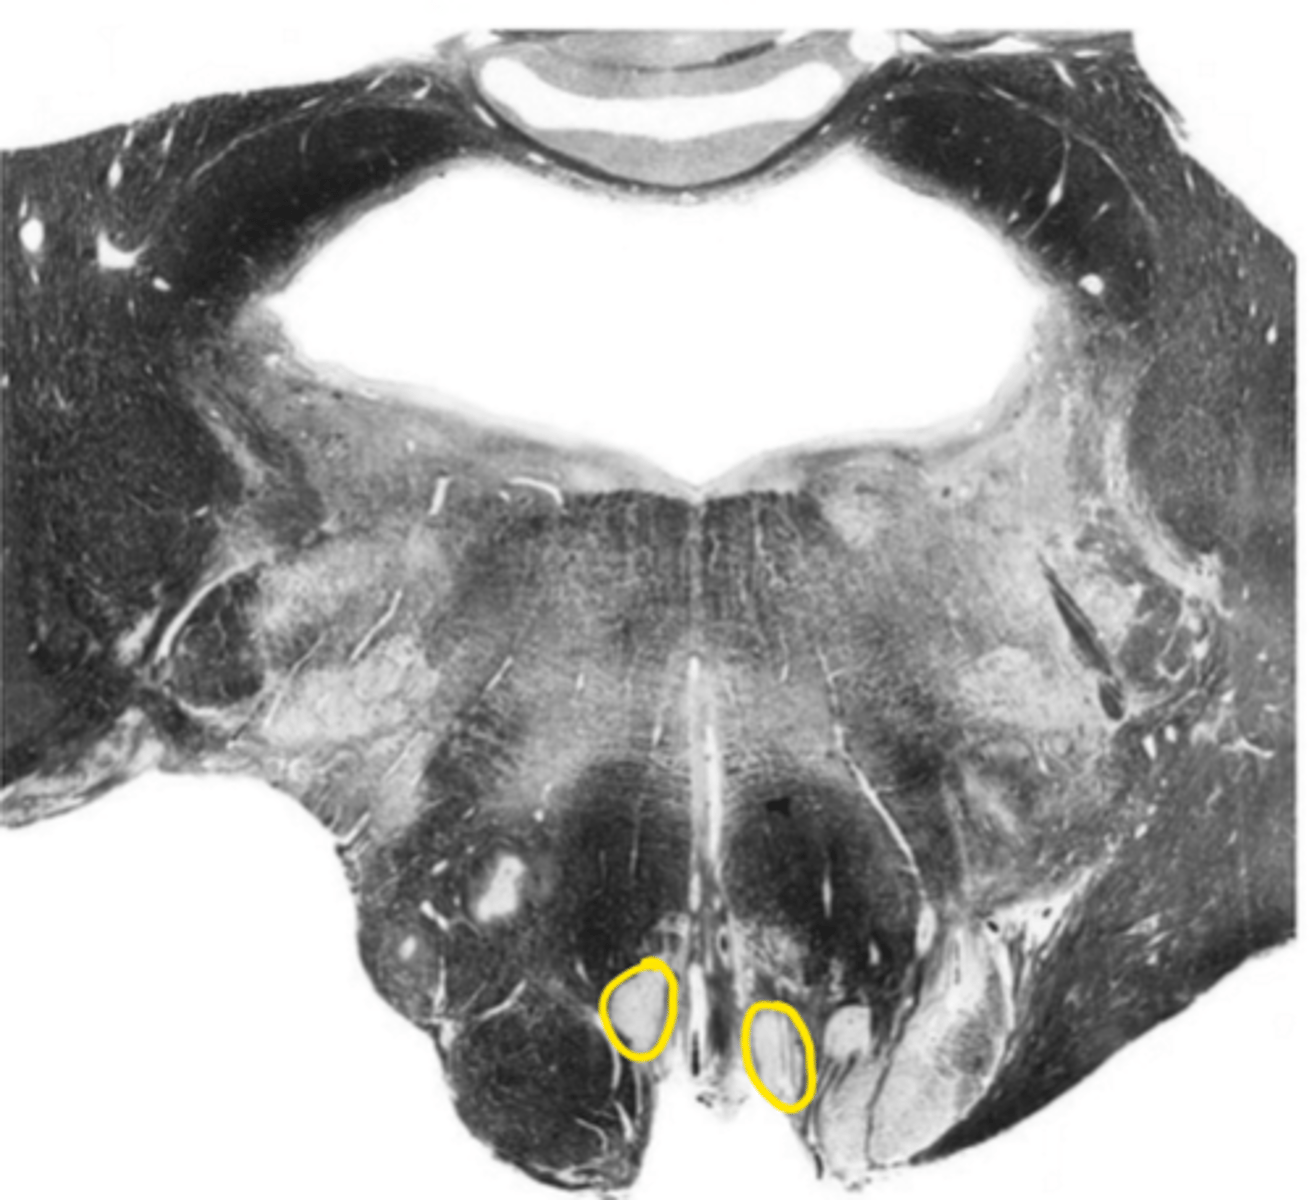

hypoglossal nucleus

ID the nucleus

vestibular nucleus

inferior cerebellar peduncles

ID the structure

reticular formation

vagus nerve

ID the nerve

principle olivary nucleus

corticospinal fibers

hypoglossal nerve

medial lemniscus

anterior median sulcus